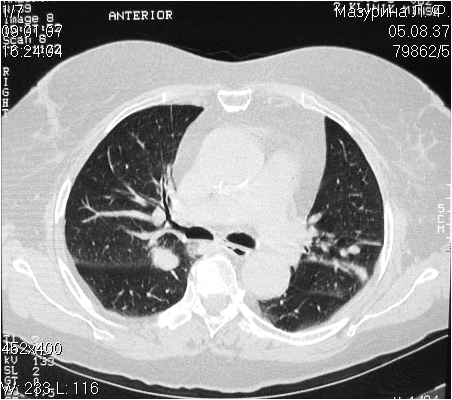

Раз уж коснулись легких, то вот другой морфологически верифицированный случай. Множественные очаговые образования(гранулемы) от 10мм до 35мм (с распадом) больше всего похожи на метастазы. Из всего приведенного д-ром Марио дифференциального ряда мне лично попадались случаи гранулематоза похожие именно на метастазы. В первый раз пролетаешь и даже не указываешь Вегенера, но потом, когда видишь гранулему с распадом(да ещё бывают размеры побольше), то уже вполне можно "угадать". А вообще (не применительно к данному случаю), больные зачастую гибнут от легочных кровотечений из таких вот распадающихся гранулем(применительно к СНГ) или, если преобладает поражение почек - от тяжелых гломерулонефритов.